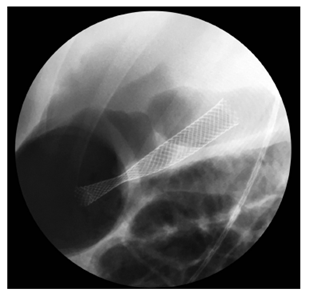

Se avanzó con guía hidrofílica de 0,33 al pseudoquiste (Figura 1).

Se retiró el cistotomo y se realizó una dilatación con balón hidrostático hasta 9 mm.

Se creó una comunicación pancreatocistogástrica sobre la guía hidrofílica.

Se retiró el balón de dilatación y se insertó una prótesis biliar metálica autoexpandible completamente cubierta de 10 mm x 80 mm cuya copa distal quedó en el pseudoquiste pancreático, el cuerpo de la prótesis en la pared gástrica y la copa proximal en la luz del estómago (Figura 2).